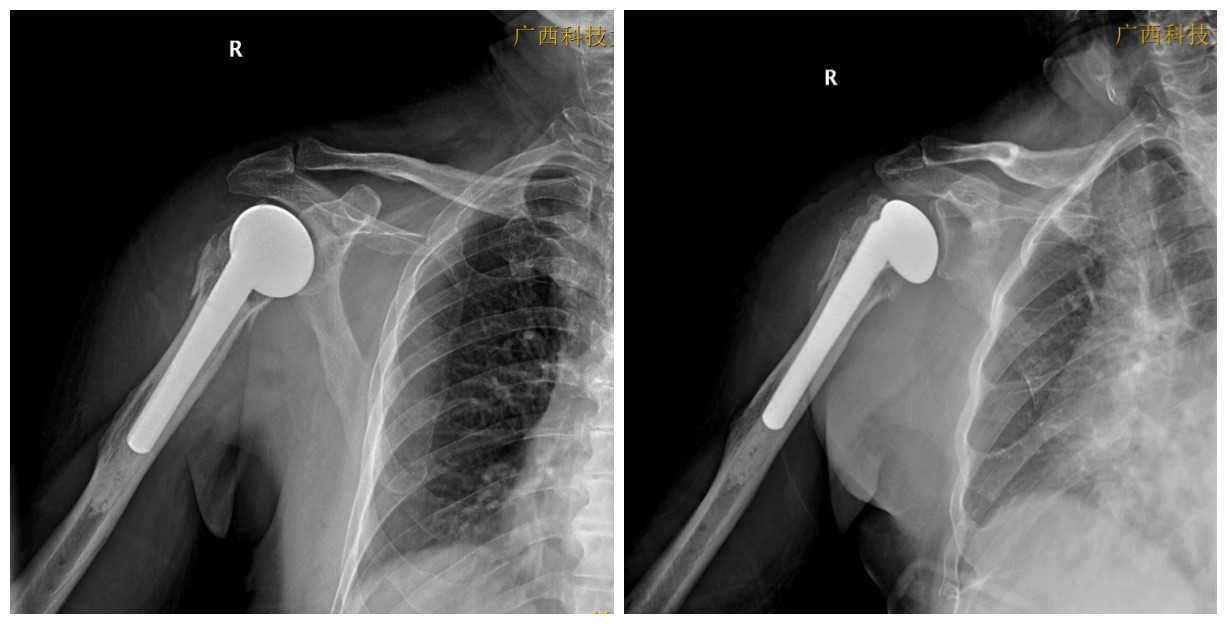

一次意外摔倒,让80多岁的阿婆右肩剧烈疼痛、活动受限,连穿衣、抬手都变得异常艰难。近日,我院关节外科/运动医学科专家赵良军副院长、覃刚主任带领团队为阿婆成功实施右侧人工肱骨头置换术,术后疼痛明显减轻,恢复顺利,为高龄复杂肱骨近端骨折患者带来更优治疗选择。

高龄摔倒致重伤,80多岁阿婆因摔倒致右肩疼痛及活动受限 7小时紧急入院。入院后完善 X 线、CT 等检查,明确诊断:右肱骨近端粉碎性骨折;骨折移位明显、骨质疏松严重,保守治疗难以复位固定,常规内固定手术风险高、效果不佳。

骨科团队全面评估病情,完善术前检查,排除手术禁忌症,与患者及家属充分沟通后,制定个体化手术方案:行右侧人工肱骨头置换术手术在全麻下顺利完成,创伤小、出血少、时间短。术后即刻:骨折端疼痛明显减轻;术后早期:即可逐步开展康复锻炼;术后复查:假体位置良好。